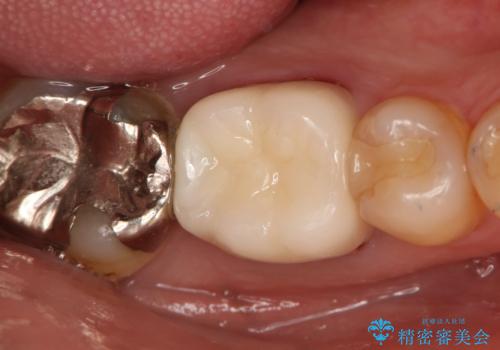

- 咬んだ時に右下奥歯に痛みがあるとの事で来院された患者様です。

歯の神経は壊死していたため、精密根管治療と補綴治療を計画しました。

セラミックでの治療を希望されたので補綴はオールセラミッククラウンでの治療を選択しました。